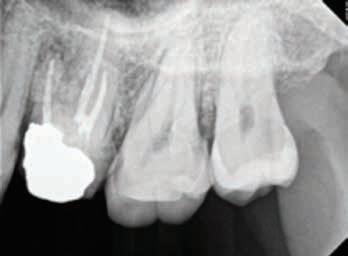

Scene Description: An unidentified Hispanic male was found by a worker mowing grass near the back parking lot of a Domino’s restaurant in Ft. Worth, Texas, on 6-28-2022. The decedent was lying unresponsive in a supine position on the pavement between a dumpster and a cargo shipping container when Ft. Worth police arrived at the scene. Video surveillance obtained from the restaurant caught the decedent moving around on camera near the dumpster at 1800 hours on 6-28-2022. The decedent was clad in pants and a belt. No signs of medical intervention were observed, and brown emesis was present around the decedent’s mouth. No foul play was suspected.

Dental Evidence Recovered: Maxilla and Mandible

Right Left

Right Lateral View

Left Lateral View

Periapical Tooth #3 (Root Canal Treatment)

Periapical Tooth #14 (Root Canal Treatment)

#3 #14